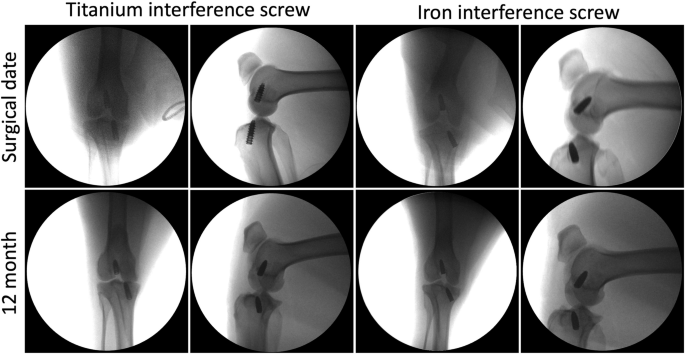

Radiographic examinations at 3, 6, and 12 months postoperatively confirm that the screws remain in their original positions without evidence of migration or loosening (Fig. 1).

Radiographic assessment of the position of titanium and iron interference screws shows no change from the day of surgery to 12 months postoperatively.